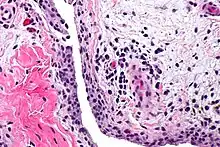

Chronic synovitis

Synovitis is the medical term for inflammation of the synovial membrane. This membrane lines joints that possess cavities, known as synovial joints. The condition is usually painful, particularly when the joint is moved. The joint usually swells due to synovial fluid collection.

Synovitis may occur in association with arthritis as well as lupus, gout, and other conditions. Synovitis is more commonly found in rheumatoid arthritis than in other forms of arthritis, and can thus serve as a distinguishing factor, although it is also present in many joints affected with osteoarthritis.[1][2] In rheumatoid arthritis, the fibroblast-like synoviocytes, highly specialized mesenchymal cells found in the synovial membrane, play an active and prominent role in the synovitis.[3] Long term occurrence of synovitis can result in degeneration of the joint.